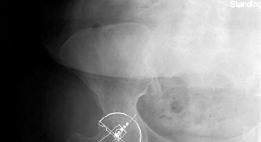

Clinical & Radiographic Imaging